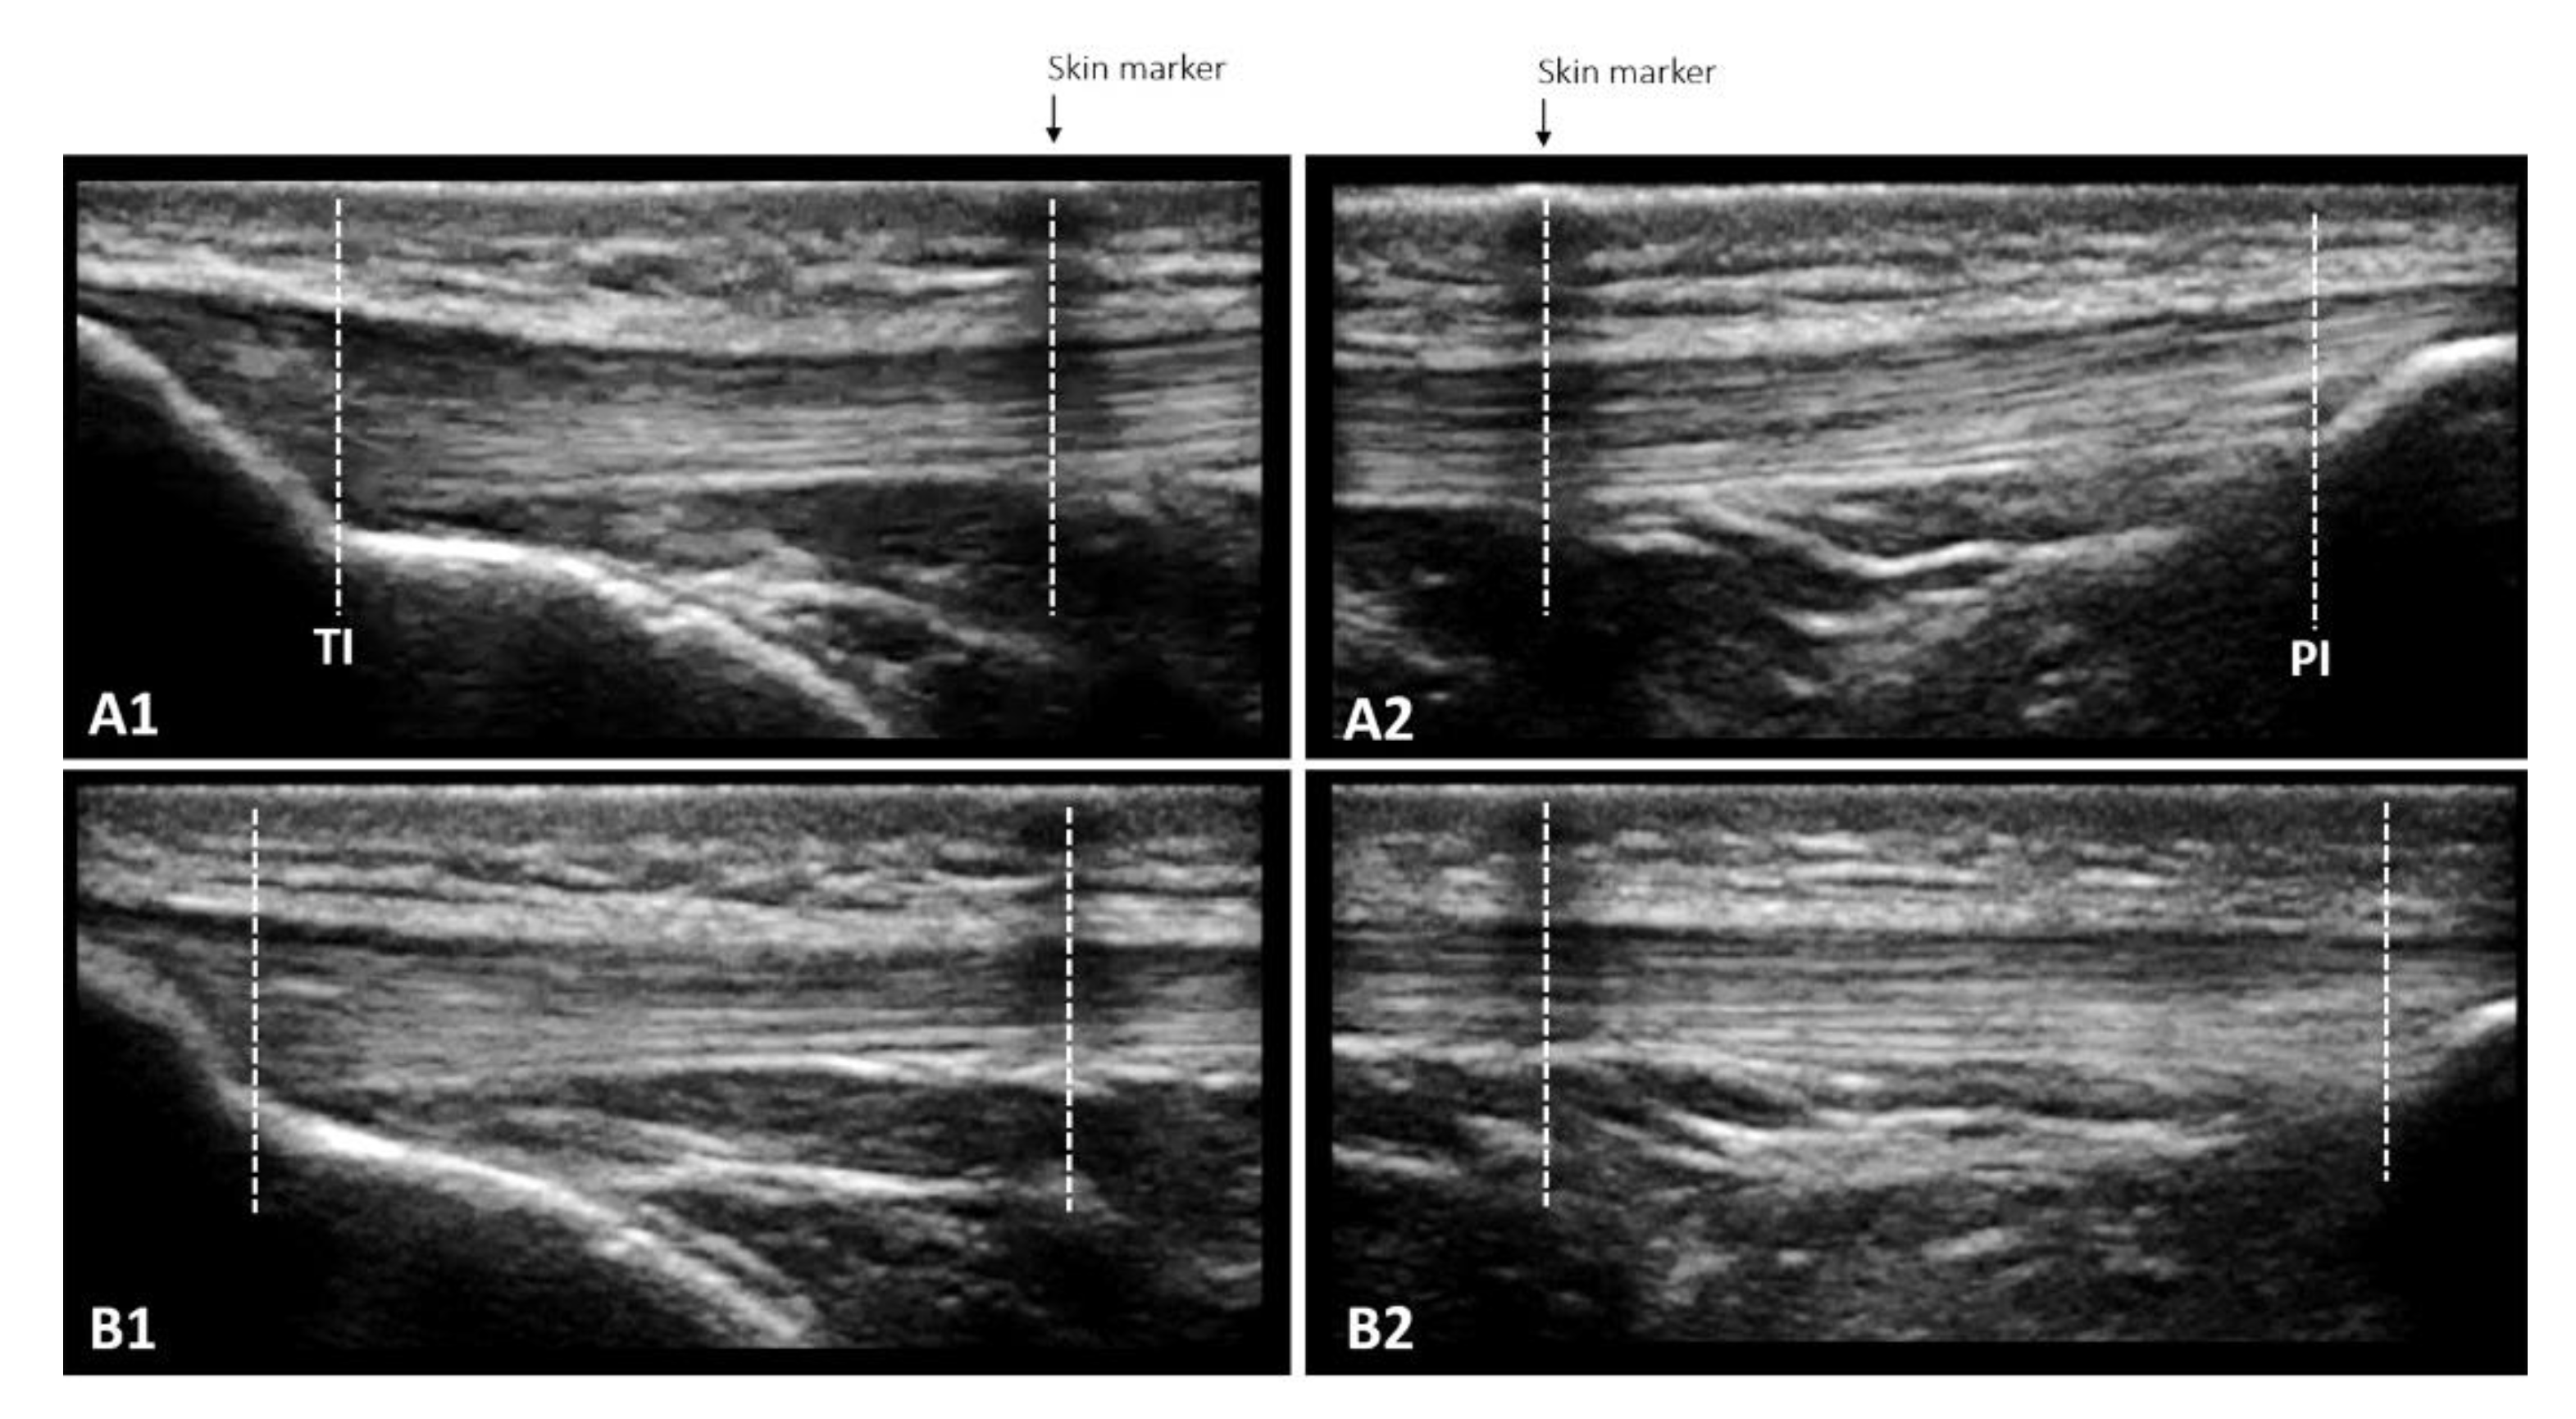

2.5.3. Muscle Architecture Assessment

2.5.4. TAC Stiffness

2.5.5. Patellar Tendon Properties